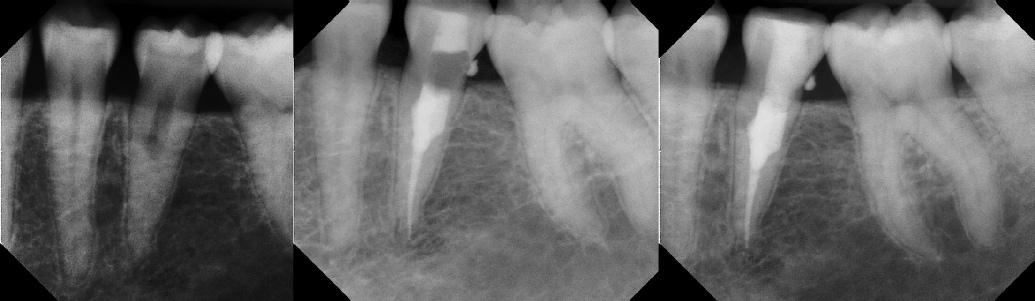

COMPLICATED ANATOMY LARGE LESIONS CALCIFIED CANALS PERFORATION / RESORPTION SEPARATED INSTRUMENTS SURGICAL CASES RETREATMENT / pOST REMOVAL OPEN APICES ACCESS THRU CROWNS Root Canal Case Portfolio

6 mos.